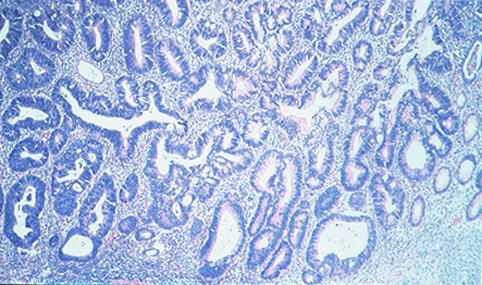

clasificación del pacienteTumor Epitelial Maligno/Adenocarcinoma

parte(separada por órganos)colon/descendente

método de exámenMicro

clasificación ectoscópica de tumoresTipo 0(tipo superficial)/Tipo I(Is)

diámetro mayor del tumor20 - 24

grado de penetraciónm